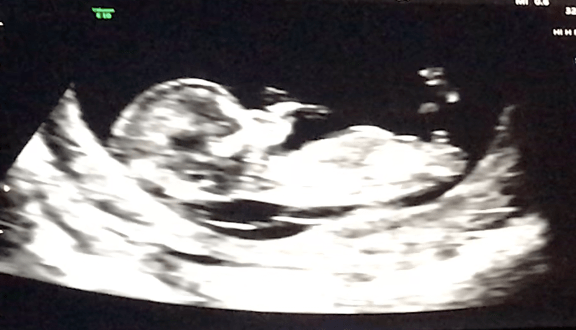

Second trimester: “The honeymoon trimester” — when morning sickness fades, energy comes back, your bump starts to show, and strangers begin smiling at you. We certainly didn’t expect to begin our second trimester at our 12-week ultrasound learning that our baby boy had a 50/50 chance of making it to term, and that if he were to make it, there was a 80-90 percent chance he would have a moderate to severe health condition.

The strength and clarity we were able to find individually and together allowed us to much more constructively process the news we would hear at our 16-week ultrasound. We both agreed that during weeks 12-16 we felt like we had been equipped with the tools we needed to support each other moving forward. In the meantime, we were comforted by the fact that Theo was and will continue to be in the safest place possible as I carry him through this pregnancy.